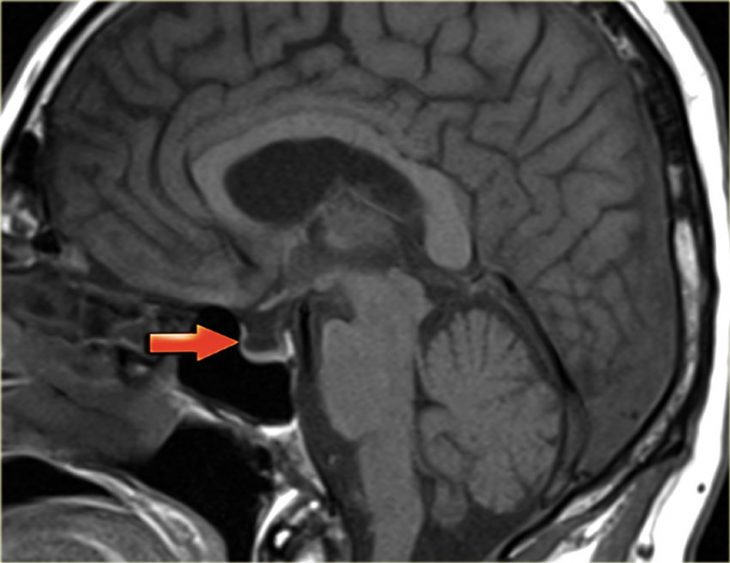

Синдром пустого турецкого седла причины симптомы лечение